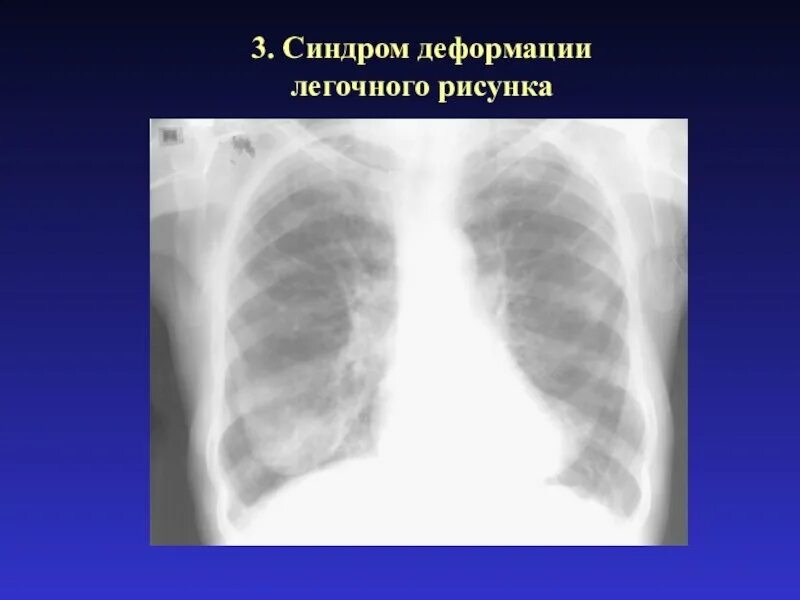

Легочный рисунок деформирован по петлистому типу